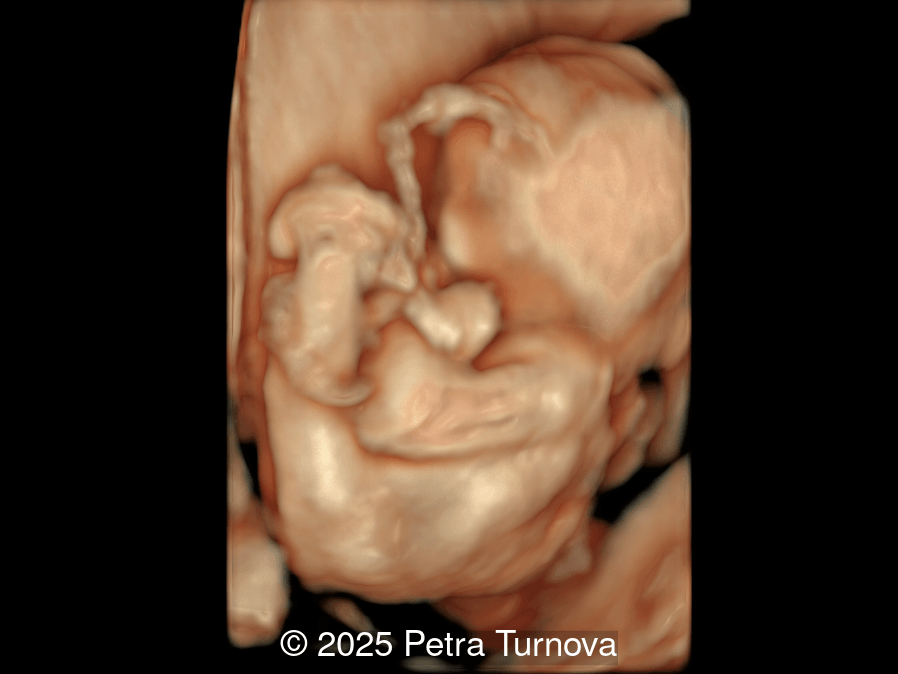

A woman with no significant medical history presented to our center at 20 weeks and 5 days for fetal anatomic survey. The following findings were observed:

Image 4

Our imaging revealed malformations in all four limbs with elbow, wrist, and knee joints fixed in extension, as well as foot and ankle malformations. Profile abnormalities were observed with prefrontal edema, flat profile and retro-micrognathia. Ultrasound demonstrated minimal stomach filling related to a lack of swallowing ability and hypoplastic lungs due to poor diaphragmatic movement. Nuchal edema was present.